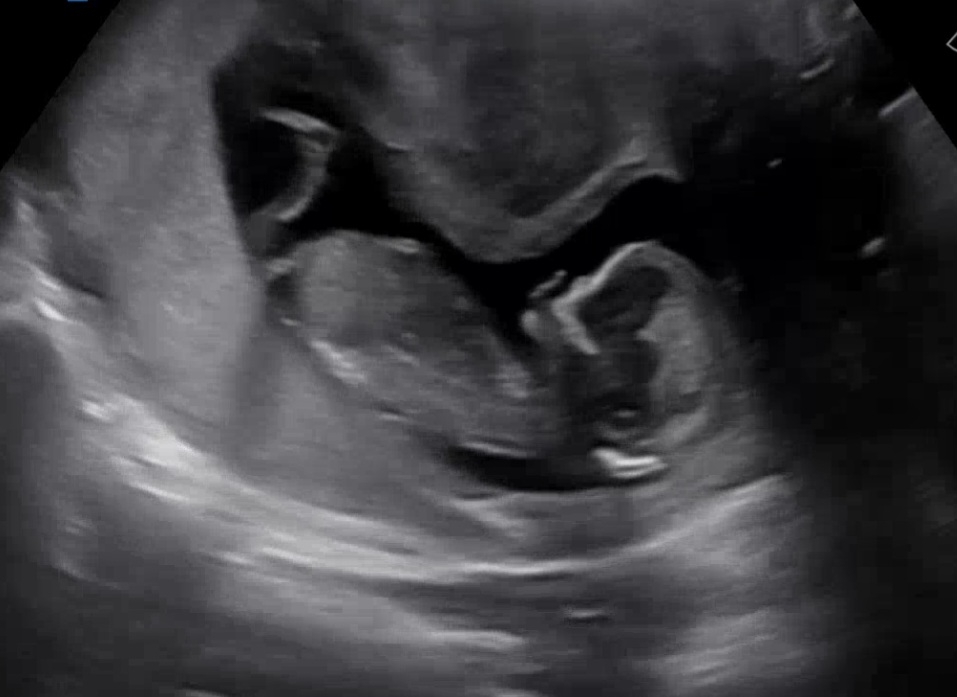

12주 5일차 각도법 궁금해요

초음파랑 입체초음파했는데 얼굴도 안보여주고 다리도 꼬고 있어요 각도법 아시는 분 예상 부탁드립니다